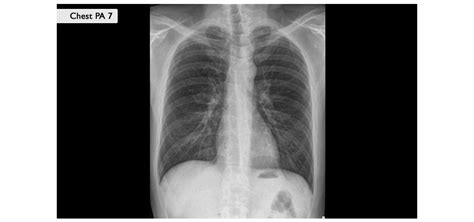

Primer ženske po prometni nesreči in zlomu medenice:Špela se je obrnila s svojo zgodbo, saj je po prometni nesreči, kjer je utrpela zlom sramne kosti, zdrobljeno križnico in počeno čašico kolka, tri leta poslušala, da bo lahko rodila le s carskim rezom. Sedaj v 38. tednu nosečnosti pa je njena ginekologinja izrazila dvom o nujnosti carskega reza. Travmatologi so ji sicer svetovali carski rez, medtem ko je ginekologinja menila, da "ploščica res ni nobena ovira, da ne bi mogla roditi po naravni poti." Špela je bila šokirana, saj jo je skrbela možnost, da se med porodom ne bo dovolj odpirala zaradi kovinske ploščice na mestu vezi, ki povezuje sramni kosti, ter zaradi poškodovane križnice.

Mag. Stanko Pušenjak, dr. med., specialist ginekolog in porodničar, je na podlagi RTG posnetka pojasnil, da medenica kot taka ni nesimetrično spremenjena in ima žensko obliko, kar bi ob povprečnih merah otroka omogočilo naravni porod. Poudaril je, da se pojem "odpiranja" nanaša na mehka tkiva, ne na kosti medenice. Svetoval je, da bi se porod moral roditi z lastnimi porodnimi silami, v primeru zastoja pa bi opravili carski rez. Poudaril je tudi, da je pomembno, da se pri takšnih primerih specialisti med seboj posvetujejo, namesto da postavijo ultimativne trditve o načinu poroda.